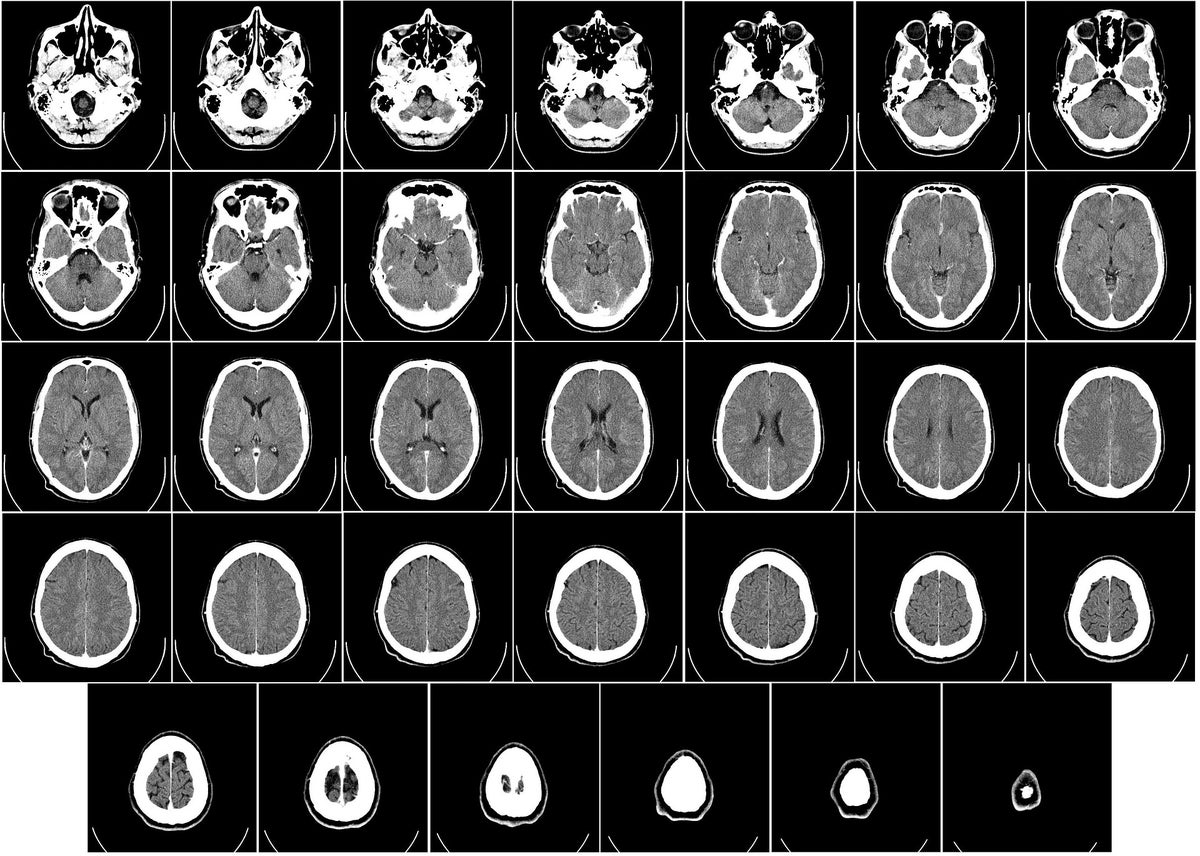

La demencia no es una enfermedad específica, sino una serie de síntomas que se presentan como producto de una pérdida en la función cerebral, la cual puede ocurrir por diversas enfermedades. Sus efectos se manifiestan en pérdida de memoria, confusión en el pensamiento, problemas del lenguaje, juicio y comportamiento.

Uno de los tipos más comunes de demencia es el Alzheimer, el cual es bastante conocido por sus efectos en la pérdida de memoria. Es más, es muy poco frecuente que la demencia o el Alzheimer se presenten en personas menores de 60 años y es solo con el paso de los años que la gente se vuelve más propensa.

Esto se debe a la falta de suficiente sueño en una persona, cuya cantidad de horas depende de la edad y género de cada quien, aumenta la producción de una proteína que se vincula con la demencia. Y es que durante el sueño, el cerebro se limpia de la proteína Beta-amiloide. Esta se ha asociado con el Alzheimer, aunque también tiene otras funciones. Si no se elimina del sistema al dormir, existe el riesgo de que cree depósitos tóxicos que causan esta enfermedad.